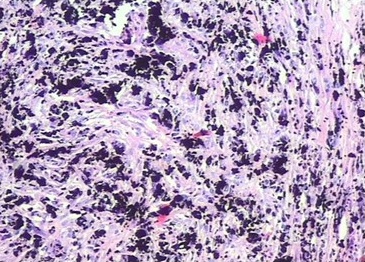

Se le realizaron cortes histológicos a la lesión extirpada para estudio anatomopatológico. (Fig. 6).

Macroscópico: espécimen rotulado como conjuntiva, que mide 2,2 x 1,5 cm, de color pardo oscuro, brillo metálico, consistencia suave, al corte de iguales características, de donde se extrae cuerpo extraño de aproximadamente 1 cm de longitud pardo oscuro (grafito).

Histología: biopsia donde se observa tejido fibroso con pigmento pardo oscuro presente en la totalidad de la muestra examinada.

Diagnóstico: pigmento exógeno.